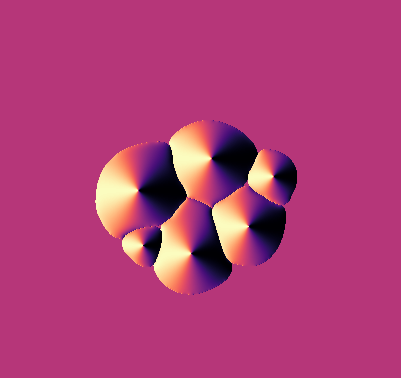

\text{Qualitative Results}